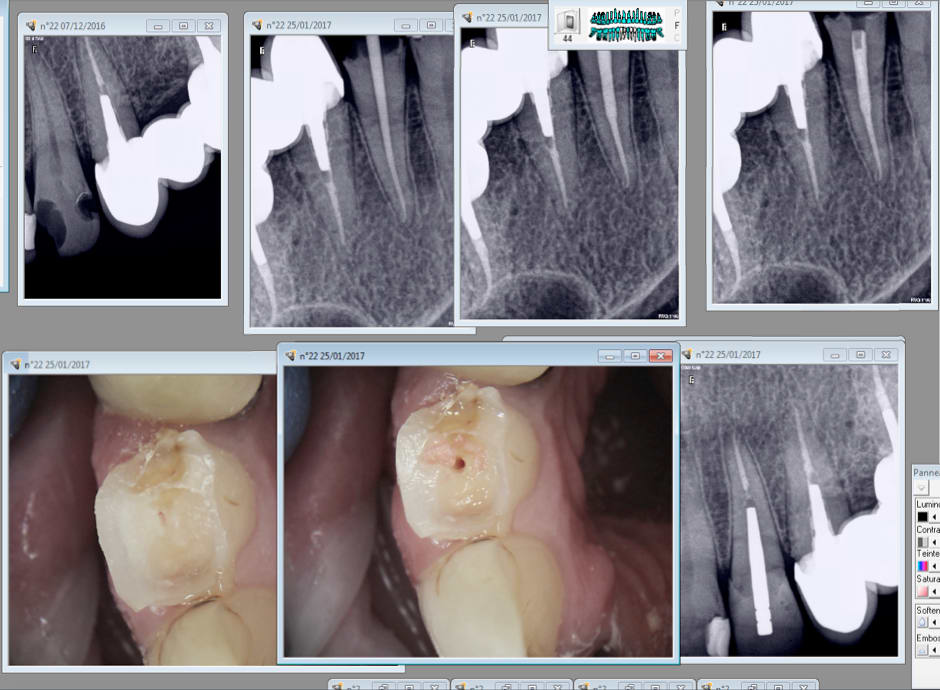

Tiens encore un exemple.

40 mn de A à Z endo taille empreinte provisoire. Et encore tu perds du temps en unitaire. Quand tu les fais en rang d'oignons tu gagnes du temps. Ca permet de réduire les couts. Ca devrait intéresser Mr Revel non ? -)